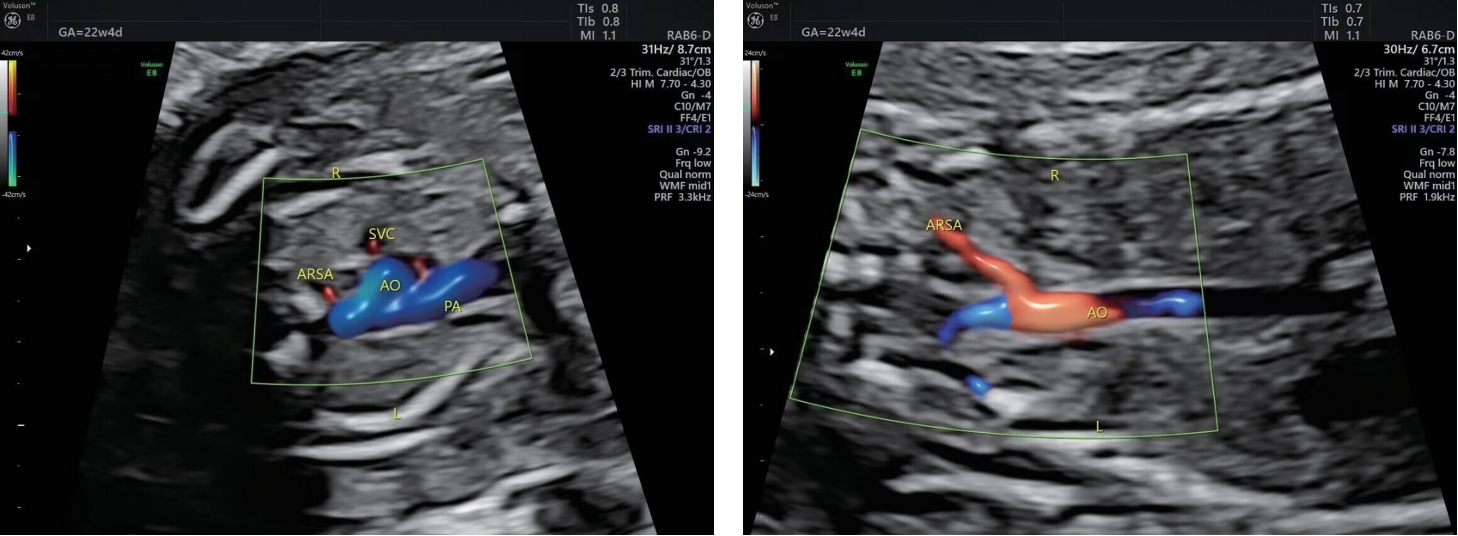

• 孕中期超声多切面检查对超重孕妇胎儿心脏畸形的诊断价值

2026, 36(4):72-77. DOI: 10.3969/j.issn.1005-8982.2026.04.012

摘要 (49) HTML (61) PDF 2.01 M (32) 评论 (0) 收藏

摘要:目的 分析孕中期超声多切面检查对超重孕妇胎儿心脏畸形的诊断价值。方法 回顾性分析2023年6月—2024年12月在商洛市中心医院超声医学科进行孕中期心脏超声检查的114例超重孕妇的临床资料,所有孕妇行超声常规和超声多切面检查,分别在平卧位、侧卧位下完成检查,以随访结果为金标准,分析超声多切面检查的诊断效能及图像质量。结果 超声多切面检查平卧位和侧卧位图像满意度均高于超声常规检查(P <0.05);侧卧位超声多切面检查和超声常规检查图像满意度均高于平卧位(P <0.05)。随访结果显示,5例(4.39%)心脏畸形胎儿中,室间隔缺损1例、三尖瓣下移畸形2例、左心发育不良1例、单心室1例。超声常规检查的敏感性为20.0%(1/5),特异性为92.7%(101/109),准确度为89.5%(102/114);超声多切面检查的敏感性为80.0%(4/5),特异性为97.2%(106/109),准确度为96.5%(110/114);两者联合检查的敏感性、特异性、准确度均为100.0%。孕22~<24周的52例孕妇中,检出心脏畸形1例(1.92%),孕24~<26周的62例孕妇中,检出心脏畸形4例(6.45%)。结论 孕中期超声多切面检查可显著提高超重孕妇胎儿心脏畸形的检出准确性,图像质量优于超声常规检查。联合多切面与常规超声检查可使敏感性、特异性及准确度均达100%,推荐作为超重孕妇胎儿心脏畸形筛查的优选方案。

• 0+1

• 1+1

• 2+1